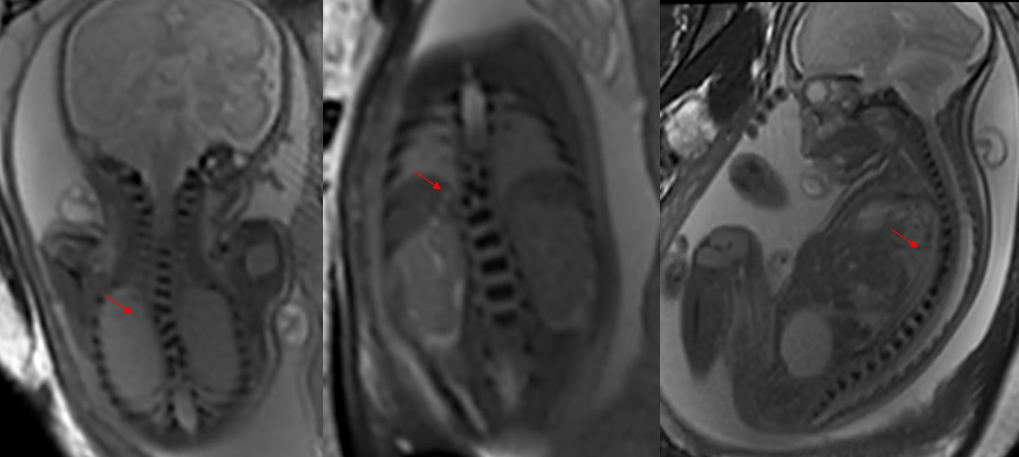

根据2012年卫生部《中国出生缺陷防治报告(2012)》白皮书指出,我国是出生缺陷高发国家之一,新生儿出生缺陷发生率约为5.6%,每年新增出生缺陷患儿约90万例,目前已知的人类出生缺陷疾病达8000—10000种。预防出生缺陷是全球重大医学课题,亦是民生健康刚需。

出生缺陷,会给家庭带来沉重的精神和经济负担,严重影响家庭的幸福和生活质量。